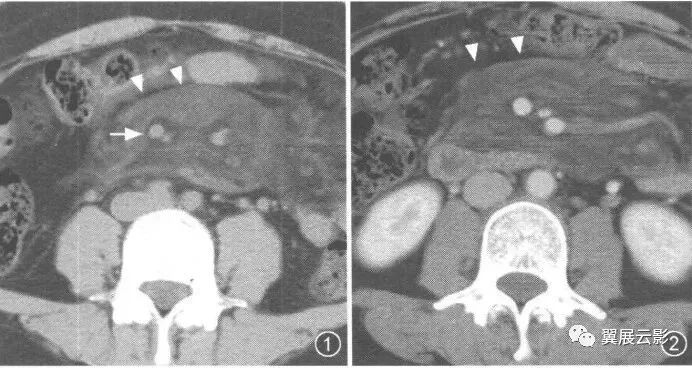

24、泪滴状肠系膜上静脉征(肠系膜上静脉变形征)

在横断面腹部增强CT及MRI,正常圆形的肠系膜上静脉受肿瘤组织挤压而变成泪滴状、线状或椭圆形。

门静脉由脾静脉和肠系膜上静脉在胰头后方汇合而成,在CT横断面上,正常胰头或其钩突与肠系膜上静脉之间有脂肪组织相分隔。当发生胰头癌时,肿瘤可向周围侵犯,突破脂肪层并向周围血管浸润。当肠系膜上静脉受到癌组织直接浸润或受到周围被累及的纤维结缔组织牵拉时,正常肠系膜上静脉的圆形断面可变为泪滴状、线状或椭圆形,肿瘤与肠系膜上静脉间的脂肪间隙消失,此征象被称为泪滴状肠系膜上静脉征。该征象的出现是判断胰头癌不可切除的可靠指征。

(该图来自《CT泪滴状肠系膜上静脉征评价胰头癌不可切除性的意义》一文, 中国医学影像技术2001年第17卷第2期)

图1 动态增强CT 示胰头部肿块紧邻 SMV、SMA,周围正常脂肪间隙消失,SMV受压呈泪滴状。

图2 螺旋增强CT 示胰钩突部一低密度肿块,SMA包绕受侵,SMV受压呈线形改变

图3 动态增强CT 示胰头部一密度不均匀肿块,与 SMV脂肪间隙消失,SMV受压呈椭圆形改变。

图4 螺旋增强CT 示胰头部一密度不均匀肿块,与 SMV脂肪间隙模糊但仍存在,三角形的 SMV为容积效应所致。